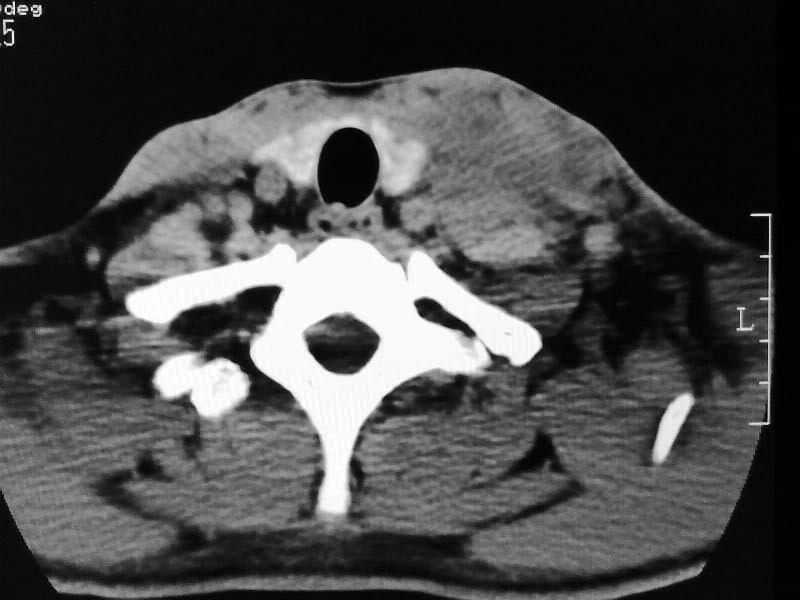

以下是引用余辉在2009-5-3 11:36:00的发言:[br]左侧胸锁乳突肌下方不规则肿物影,边界不清,内部密度不均,左侧颈外侧区脂肪增多,多发淋巴结肿大,考虑淋巴或神经来源肿瘤可能性大,不除外淋巴结炎,肌源性肿瘤及增生性肌炎等,活检